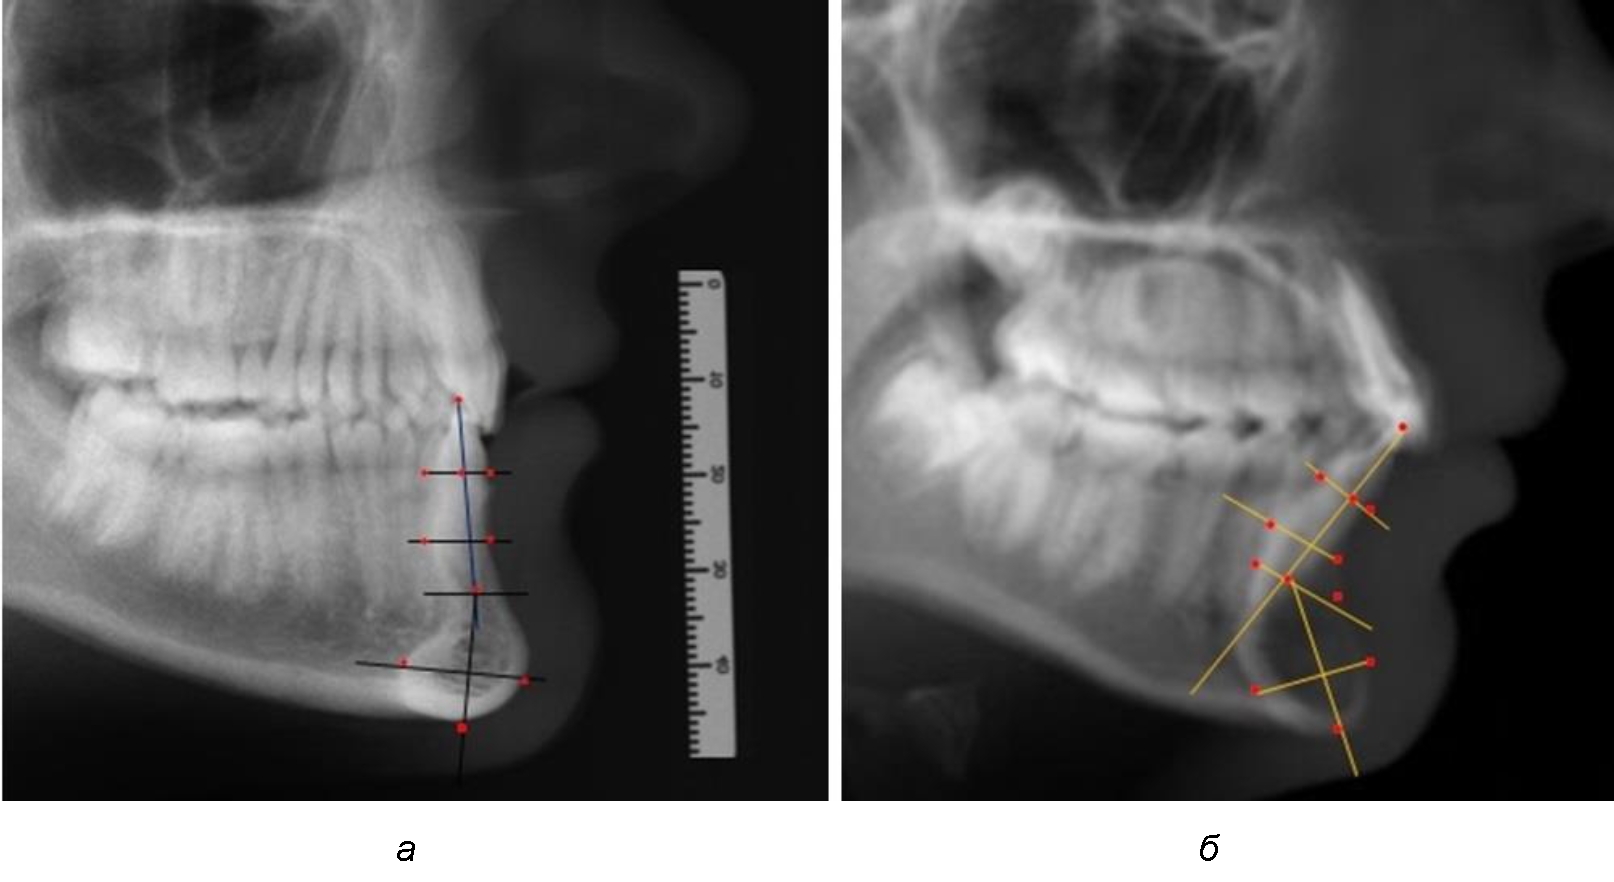

При анализе полученных данных обращает на себя внимание факт того, что из вертикальных параметров зубоальвеолярной части сегмента наиболее вариабельным является размер между апикальными точками Downs и Schwarz (BSM–B), который составлял (6,79 ± 0,54) мм, при величине сигмального отклонения – 2,35. Также большая ошибка репрезентативности и сигмальное отклонение было отмечено при оценки ширины подбородочного выступа. В связи с этим встречались варианты резцовых сегментов нижней челюсти различные как по ширине, так и по высоте, а также по расхождению положения апикальных точек по Downs и Schwarz (рис. 3).

Рис. 3. Варианты среднего (а), широкого (б) и узкого (в) нижнечелюстного резцового сегмента

Варианты резцовых сегментов нижней челюсти различные как по ширине, так и по высоте, а также по расхождению положения апикальных точек по Downs и Schwarz представлены на рис. 4.

Рис. 4. Особенности нижнечелюстного резцового сегмента на ТРГ у людей при среднем (а), широком (б) и узком (в) вариантах

Нередко отмечается деформация подбородочного выступа и различное его положение по отношению к зубоальвеолярной части сегмента. При мезиальной окклюзии нередко нижняя подбородочная точка смещается кзади по отношению к условной срединной вертикали нижнего резца, а при дистальной окклюзии отмечается компенсаторное отклонение подбородка кпереди (рис. 5).

Рис. 5. Особенности нижнечелюстного резцового сегмента на ТРГ у людей при мезиальной (а) и дистальной (б) окклюзии

Кроме того, так же как и у людей с физиологической окклюзией, определялось различие в положении апикальных точек Downs и Schwarz, что, по нашему мнению, может определять тактику лечения патологических форм протрузии/ретрузии резцов с учетом биотипа костной ткани.